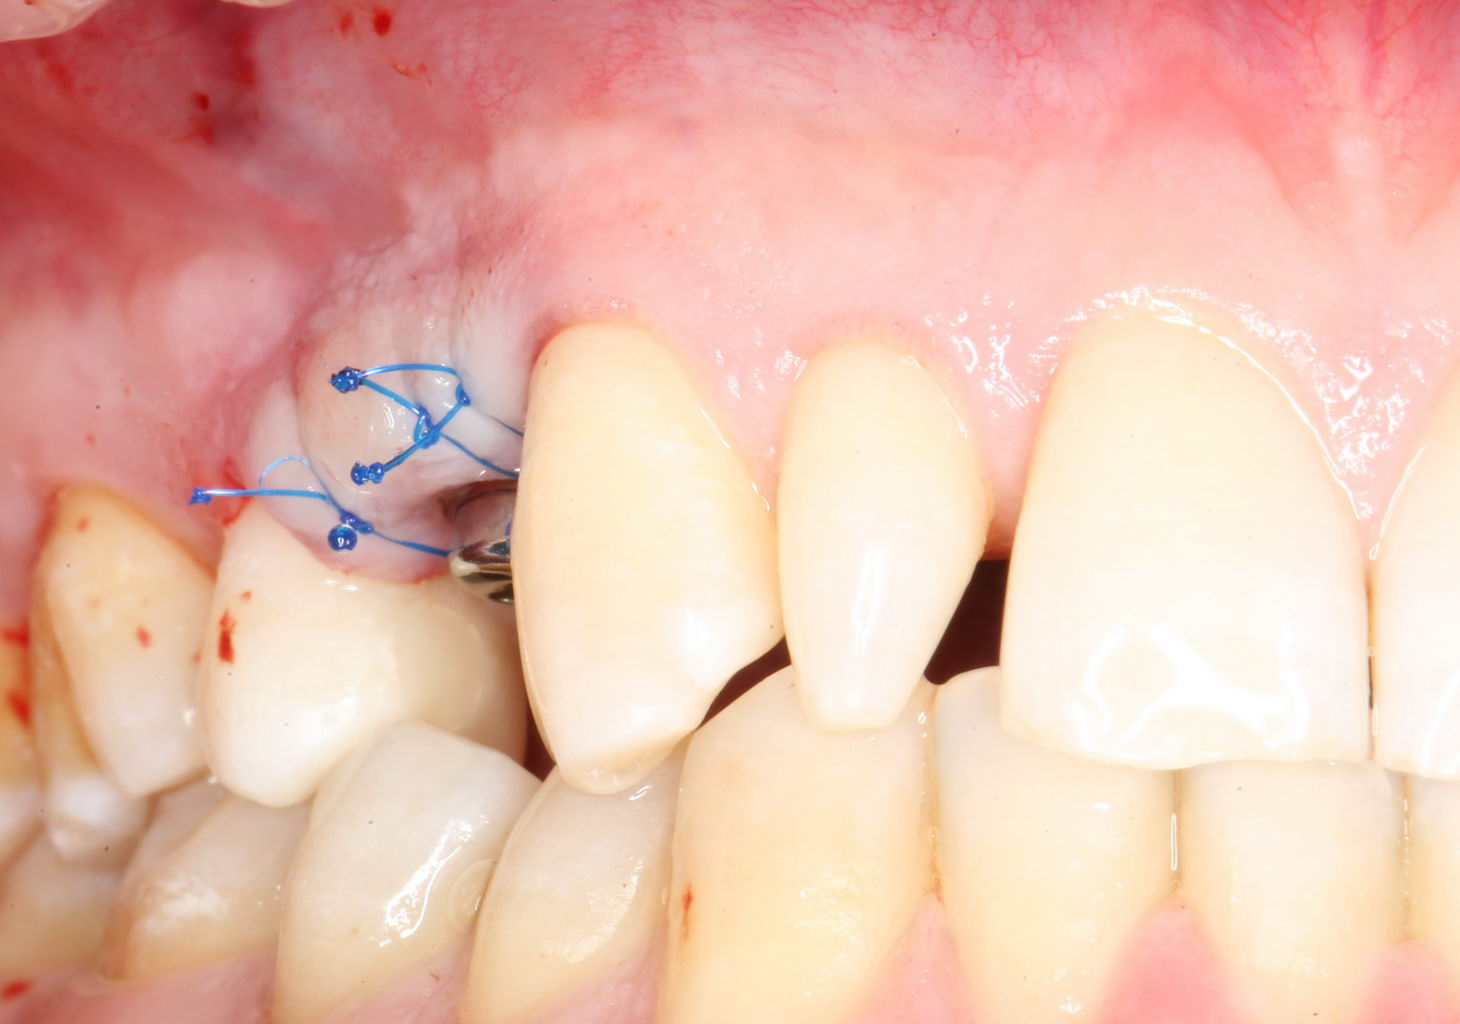

Установка формирователя десны.

Одномоментная установка формирователя десны позволяет сократить время и удешевить лечение — ведь по мере интеграции имплантата мы получаем нормально сформированный контур десны, готовый к установке протетической конструкции. Но это возможно лишь тогда, когда с объемами мягких тканей в области имплантата всё в порядке. То есть, как раз в нашем случае.

В CLINIC IN используют только одноразовые формирователи и только один раз:

С учётом клинических условий, мы подобрали к установленному имплантату формирователь Slim (без расширений) высотой 3 мм:

Для окончательного формирования десневого контура, осталось только наложить швы.

Наложение швов.

Помните, в самом начале операции мы планировали наложение швов с учётом будущего вестибулярного смещения лоскута? Так вот, теперь у нас есть возможность не просто сместить, но и зафиксировать вестибулярный лоскут. Делается это, так сказать, с подворотом края снаружи:

Обратите снимание, что альвеолярный отросток в этой области стал более объемным. Этого удалось добиться без всяких остеопластических операций или гингивопластики, путём простого перемещения тканей.